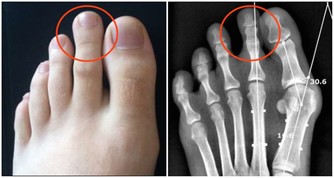

***(二)腿腳莫名的疼痛***

如果腿部血管出現硬化,那麼最明顯的表現就是莫名疼痛。可能一些輕微的血管硬化,在我們行走時會出現痛感,如果稍作休息就會有所緩解,但是一些程度比較嚴重的血管硬化,它的痛感非常明顯,如果放任不管,最終就會形成間歇性跛行。